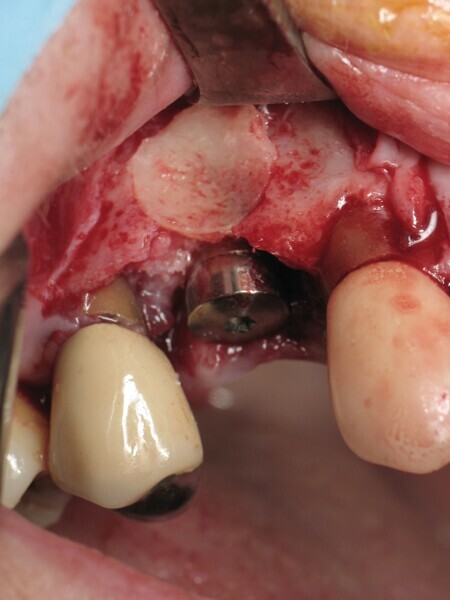

Après extraction de la première prémolaire maxillaire fracturée (Fig. 1), le soulèvement d’un lambeau a mis en évidence une perte osseuse vestibulaire sur toute la hauteur de la racine (Fig. 2). Cette lésion en « V » est rendue circulaire par un trépan de diamètre 5 mm (Fig. 3). Cela correspond au calibrage du défaut (Fig. 4). Le site d’extraction est parfaitement cureté. Le forage implantaire est réalisé contre la corticale palatine de l’alvéole d’extraction, au-delà de l’apex, pour permettre l’ancrage du futur implant. Le placement tridimensionnel de celui-ci est primordial par rapport aux collets anatomiques des dents adjacentes, ainsi que dans le sens mésio-distal et vestibulopalatin.3

Il ne faut surtout pas être piégé par la hauteur d’os perdu et enfouir plus l’implant. Un tissue level est parfaitement stabilisé grâce à ses dernières spires. (Implant TL Straumann SP 4,1 RN, longueur 12 mm SLActive). Une incision limitée en étendue et en forme de « H » est réalisée dans le secteur de la dent de sagesse inférieure, pour un abord crestal. Un trépan de diamètre supérieur au trépan de calibrage (Fig. 5), donc 6 mm dans ce cas, permet de prélever une carotte de 4 mm de profondeur (Fig. 6). Elle forme un bloc circulaire cortico-spongieux qui est impactée en force, transversalement à l’implant (Fig. 7). La surface SLActive de l’implant est au contact de l’os spongieux richement vascularisée et la partie corticale protège cet ensemble et referme parfaitement le défaut osseux (Fig. 8). L’os greffé est entouré par l’os du site receveur sur tout le pourtour. Son immobilité totale permettra sa consolidation et sa revascularisation.4 Il n’est pas utile d’enfouir l’implant ni d’utiliser une membrane, car il n’y a pas de substitut osseux (Fig. 9). La couronne définitive est réalisée à trois mois (Fig. 10). Le suivi de cette patiente montre un excellent comportement ostéo-gingival à dix ans, tant radiologiquement (Fig. 11), que cliniquement (Fig. 12).